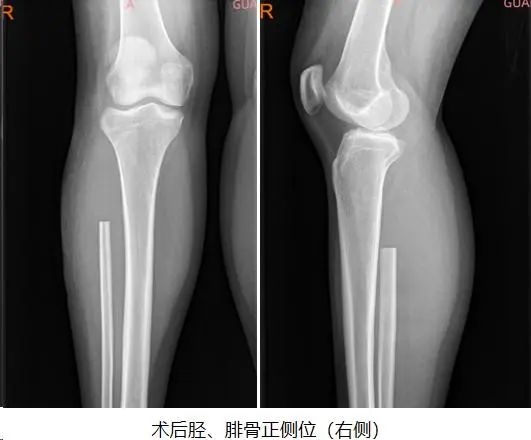

3D打印假体费用相对较高,对于一个普通的工薪阶层家庭来说,家庭经济承受能力是个问题;考虑到小英还很年轻,郑鸿主任医师团队决定从患者实际需求出发,制定了个体化手术方案,选择骨科难度较高的术式之一—左侧桡骨远端瘤段广泛切除+对侧自体腓骨移植重建术。

通过精心护理,患者第3天已下床拄拐活动,左前臂石膏托外固定,右小腿功能恢复良好。术后第10天小英就办理了出院手续。